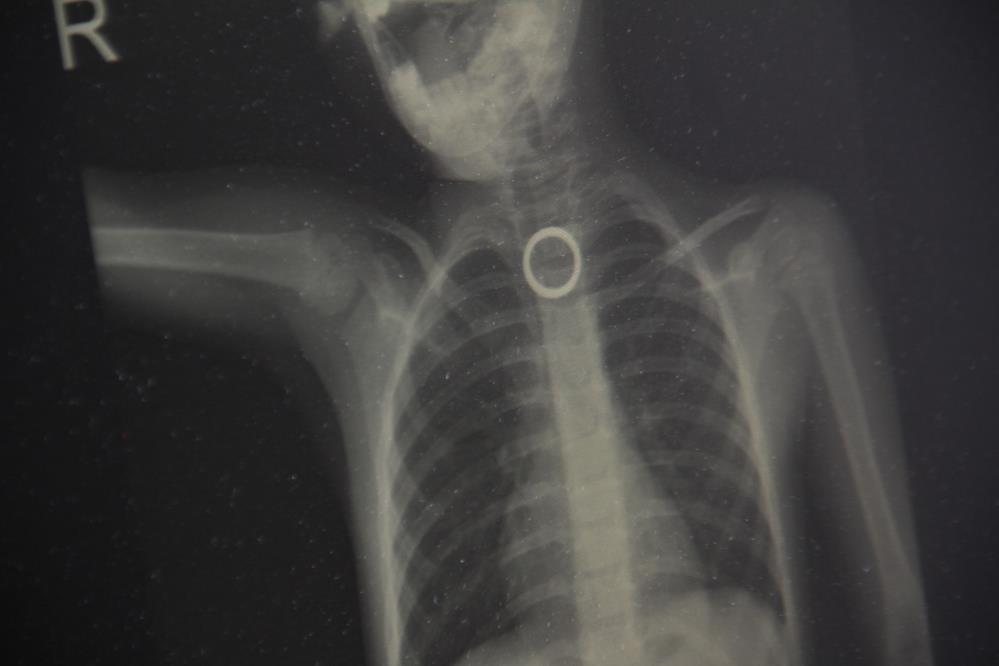

Elazığ’da 3 yaşındaki çocuğun yutması sonucu yemek borusuna sıkışan yüzük, yapılan cerrahi operasyonla çıkartıldı.

Elazığ’da evde oyun oynayan 3 yaşındaki çocuk, yakınında bulunan yüzüğü yuttu. Durumu fark eden ebeveynler çocuğu hemen Fırat Üniversitesi Hastanesine getirerek Çocuk Gastroenteroloji Ana Bilim Dalı Başkanı Prof. Dr. Yaşar Doğan’a gösterdi. Burada yapılan tetkiklerde yutulan yüzüğün yemek borusu birinci darlık kısmında takılı kaldığı görüldü. Hemen Çocuk Endoskopi Ünitesine alınan 3 yaşındaki çocuğun boğazındaki yüzük yapılan endoskopik yöntemle çıkartıldı. Sağlık durumu iyi olan çocuk taburcu edilirken, uyarılarda bulunan Çocuk Gastroenteroloji Ana Bilim Dalı Başkanı Yaşar Doğan, bu tür vakaların meydana gelmemesi için ailelerin, çocukların etrafından bulunan yabancı cisimleri uzaklaştırmaları gerektiğini belirtti.

Hastanın 3 yaşında olduğunu belirten Çocuk Gastroenteroloji Ana Bilim Dalı Başkanı Prof. Dr. Yaşar Doğan, “Bu hastamız akşam saatlerinde boğazına yabancı cisim yutma yakınmasıyla ailesi tarafından hastanemize getirildi. Yaptığımız incelemeler neticesinde özellikle yemek borusunun birinci darlık kısmında yüzüğü benzer bir yabancı cisim gördük. İlk geldiğinde hasta yeni beslendiğinden dolayı endoskopi için açlık süresi bekletildi. Ondan sonra gerekli olan endoskopi işlem yapılarak oradaki yabancı cisim çıkartıldı. Çıkarma işlemi başarılı bir şekilde yapıldıktan sonra aile 2 saatlik gözlemden sonra evine gönderildi. Şu anda herhangi bir sıkıntısı yok. Bu gibi vakalar bize çok fazla gelmektedir. Özellikle mevsimler değişkenlik dönemlerinde evlerde temizliğin yapıldığı dönemlerde ailenin çocuğu rahatlıkla gözlemleyemediği dönemlerde çocuklar etrafında buldukları her yabancı cismi ağızlarına götürme eylemindeler. Özellikle yabancı cismin nefes borusu veya akciğer kaçması ölümcül nedenlere yol açabilir ama yemek borusu veya sindirim sistemine kaçmış olan yabancı cisimler erken getirildiği zaman endoskopik yöntemlerle çıkarabilmekteyiz. Bu tür vakaların meydana gelmemesi için ailelerin tam bilinç seviyesi yerine gelmemiş çocukların etrafında yutabilecekleri bütün yabancı cisimleri uzaklaştırması gerekir. Yoksa çok kötü sonuçlarla karşılaşabiliriz” dedi.